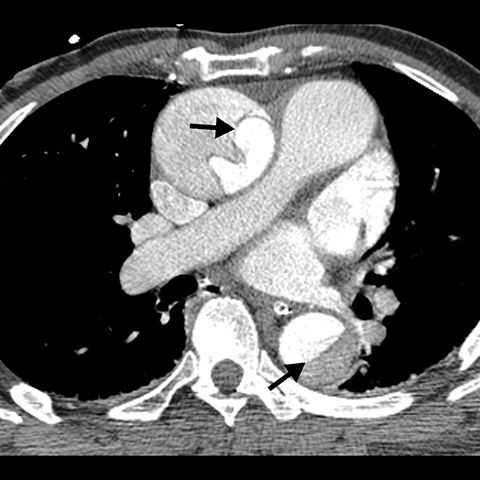

Aortic Dissection (Axial CT) [1 of 3]